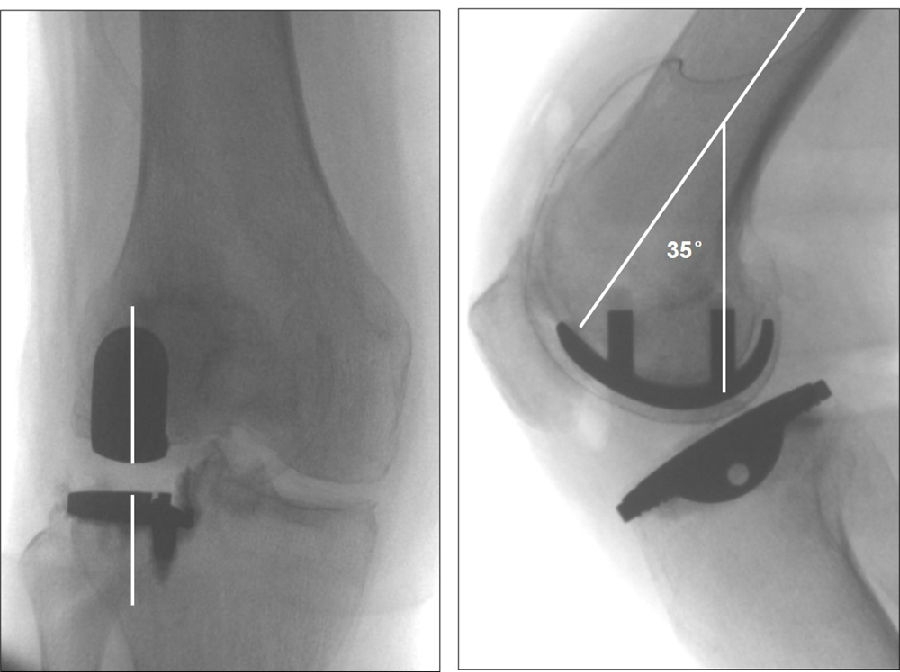

关键技术1:矢状位:无过屈、过伸

避免:股骨假体过屈,前缘凸起,发生髌骨撞击

避免:股骨假体过伸,前缘嵌入,发生髌骨弹跳

理想假体位置 A.股骨假体 胫骨假体中心线一致;B.股骨假体固定栓与后侧皮质呈35-40°

理想假体位置即前缘平稳过渡,后缘包容很好且不超出。